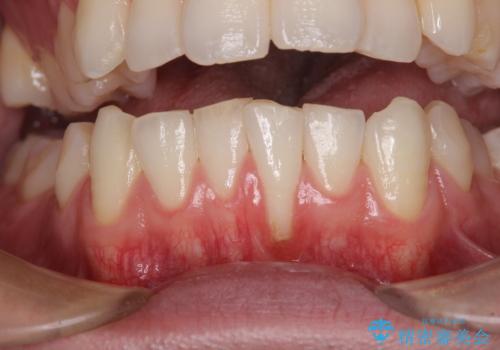

- 徐々に歯根が見えるようになり、気がついたら歯根のほぼ全てが見えるようなってしまったと言うことで来院された患者様です。

しみる症状はないものの、見た目が著しく悪く、汚れが溜まりやすいとのことで、歯肉移植による根面被覆を行うこととしました。

歯肉が非常に薄く、必要な被覆量が多いことから、1度の処置では十分な被覆は難しく、2度処置を行うことになる可能性が高いとお伝えしました。